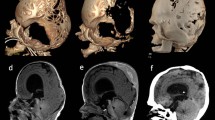

A male infant from non-consanguineous Myanmar parents with no family history of craniofacial disease was born term at 37 weeks of gestational age. He was referred to Siriraj Craniofacial Centre at the age of 1 month due to a trilobed head with tense bulging of the anterior fontanelle (Fig. 1). The overnight oxygenation monitoring showed significant desaturations, and continuous oxygen treatment was initiated. The physical examination also showed receded supraorbital rims, bilateral eye proptosis, mid-face hypoplasia, and bifid uvula. All hands and extremities were unremarkable. The fundoscopy revealed no papilloedema. The laryngotracheobronchoscopy revealed unremarkable and no tracheomalacia.

A, B, C Preoperative images demonstrating trilobar head shape and multisuture craniosynostosis. The metopic suture is patent. D Intraoperative posterior cranial decompression by wide craniectomy and foramen magnum decompression. The dotted line shows the area for foramen magnum decompression. E, F Postoperative images 4 months postoperatively show improved posterior cranial shape with remarkable bone reformation and expanded posterior cranial fossa. The fused metopic suture was observed with the upward and medial deviation of the bilateral supraorbital area

The 3D CT showed multisuture craniosynostosis involving coronal, sagittal, and lambdoid sutures. Temporal lobes were extruding through the splaying of the squamosal sutures and bulging of the brain parenchyma through the open anterior fontanelle, consistent with a cloverleaf skull deformity. There was an effacement of subarachnoid spaces and mild hydrocephalus. Further genetic testing by whole exome sequencing revealed heterogenous c.278C > G mutation with p.Ala93Gly of the SIX3 gene.

The child underwent lateral tarsorrhaphies for proptosis eye management. The posterior cranial decompression by wide craniectomy was performed along with foramen magnum decompression at the age of 2 months (Fig. 1). This involved a meticulous dissection of the bony spicules projection into the dura, resulting in a wide bony excision from just posterior to the fused coronal ring of sutures back to and including the posterior rim of the foramen magnum. The intraoperative blood salvage was used to reduce the transfusion to 35 ml. One month after surgery, the shape of the head appeared rounder and more expanded posteriorly (Fig. 2A, E). Despite this decompression, the hydrocephalus has been progressive and managed by undergoing a programmable ventriculoperitoneal (VP) shunt 2 months after the primary cranial surgery.